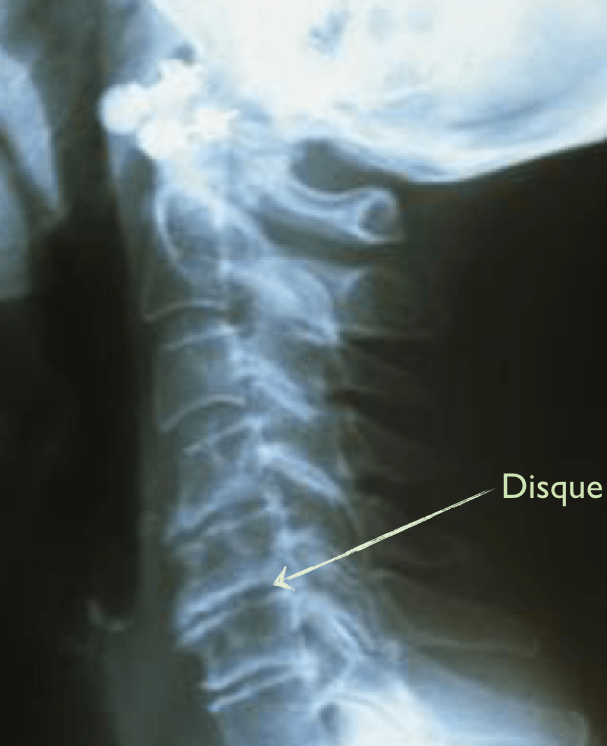

Disques pas innervés. Rectitude colonne cervicale Publié 4 octobre 2013 à 607 × 746 dans Les disques et vos douleurs ← Précédent Suivant → J’aime chargement… Poster un commentaire ou un rétrolien.